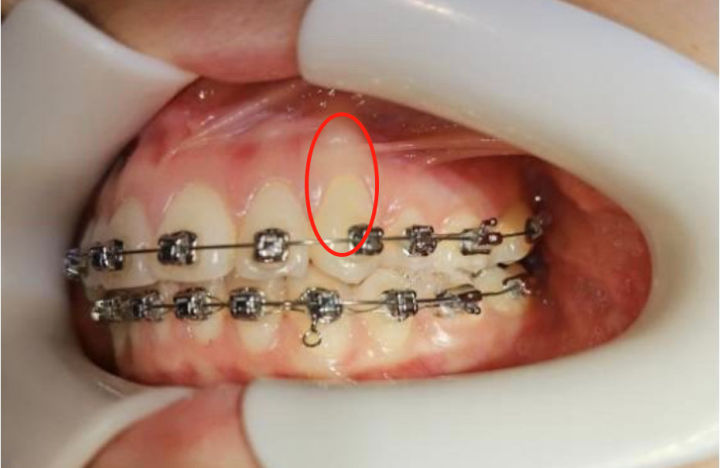

《正畸案例41:正畸中的骨开裂与骨开窗》

图片尺寸1920x1440